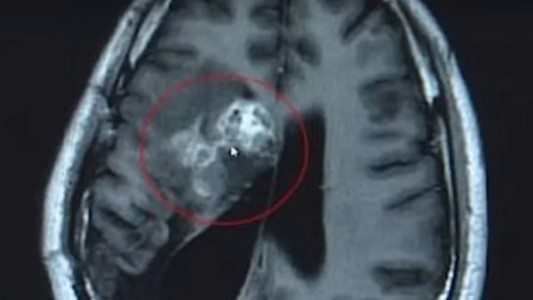

La madre que se enteró que tenía un cáncer muy agresivo y tomó una conmovedora decisión por sus hijos